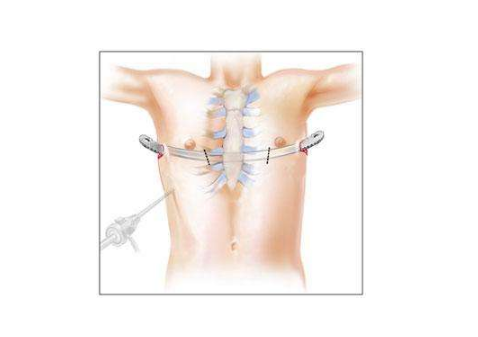

A:小兒漏斗胸的治療主要是以手術治療方式為主,臨床上可分為傳統手術方法以及微創矯形手術。傳統的手術包括胸骨翻轉術以及胸肋抬舉術兩種, 但是對於傳統手術,對孩子的創傷比較大。所以臨床上,目前採用微創漏斗胸矯形手術的方式比較多,是將塑形好的合金鋼板……